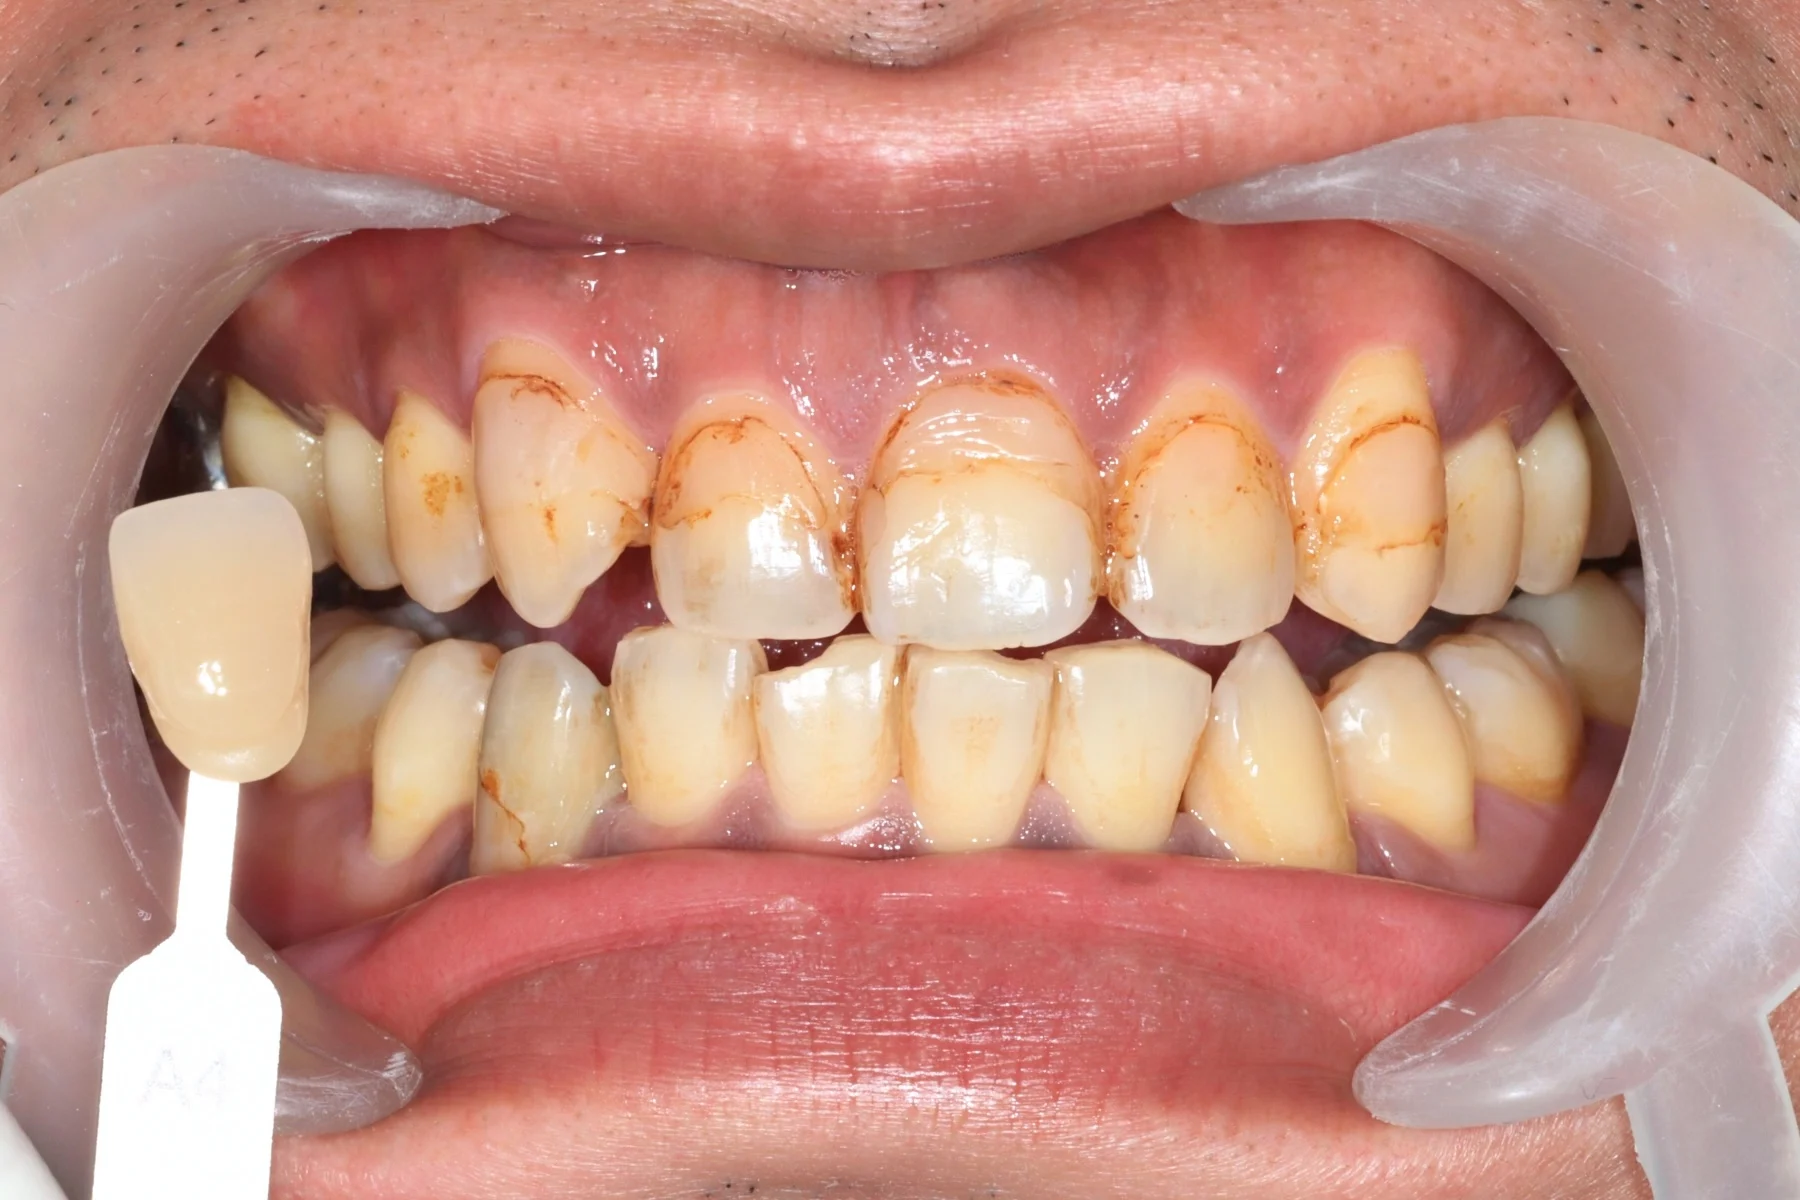

Dentist 陳昕 全口照護醫師 看診項目 前牙美學仿生樹脂補牙/全科牙醫 學經歷 臺北醫學大學牙醫系學士 前天主教新店耕莘醫院醫師 前臺北榮民總醫院醫師 亞洲齒列再生研究學會Advance植牙補綴專科訓練 微光私塾牙周雷射微創治療技術訓練 臺灣牙醫顯微美學治療學會會員醫師 中華審美牙醫學會會員醫師 CASE 案例分享 滲透型樹脂修復 主治醫師 陳昕 治療時間 單次療程 主訴 想處理前牙白白的色斑 前牙美學/仿生美學樹脂 主治醫師 陳昕 治療時間 單次療程 主訴 牙齒整齊,但門牙中間縫隙明顯,影響笑容美觀 前牙美學/陶瓷貼片 主治醫師 陳昕 治療時間 約1個月 主訴 兩顆門牙缺角,想要重建外觀 前牙美學/滲透型樹脂修復 主治醫師 陳昕 治療時間 單次療程 主訴 門牙有長期存在的白斑與表面不平整,影響外觀與自信 前牙美學/仿生美學樹脂 主治醫師 陳昕 治療時間 約兩週 主訴 矯正後的黑三角縫問題 前牙美學/仿生美學樹脂 主治醫師 陳昕 治療時間 約三週 主訴 因牙周病產生的黑三角縫 前牙美學/牙冠增長術、仿生全瓷牙冠 主治醫師 陳昕 治療時間 約6個月 主訴 牙齒排列不整、假牙外觀不自然 前牙美學/仿生美學樹脂 主治醫師 陳昕 治療時間 約兩週 主訴 露齒笑時黑三角縫明顯,覺得不好看 前牙美學/仿生美學樹脂+噴砂美白 主治醫師 陳昕 治療時間 約兩週 主訴 露齒笑時有不好看的黑三角縫,容易有茶垢沉澱,讓縫隙更明顯 牙齒美白/噴砂美白+冷光美白 主治醫師 陳昕 治療時間 單次療程 主訴 前牙泛黃且染色明顯,影響外觀與自信 牙齒美白/噴砂美白 主治醫師 陳昕 治療時間 單次療程 主訴 牙齒表面有喝咖啡、抽菸造成的外部染色,影響外觀與自信 點此載入更多 Column 精選文章 FEATURED 精選案例 【牙科修復案例】陶瓷貼片可以做一顆嗎?單顆門牙缺角修復,陶瓷貼片重建自然笑容 2026-01-16 從「假笑」到「自然笑容」的轉變——認識「牙冠增長術」與「仿生全瓷冠」 2025-10-14 Video 精選影音